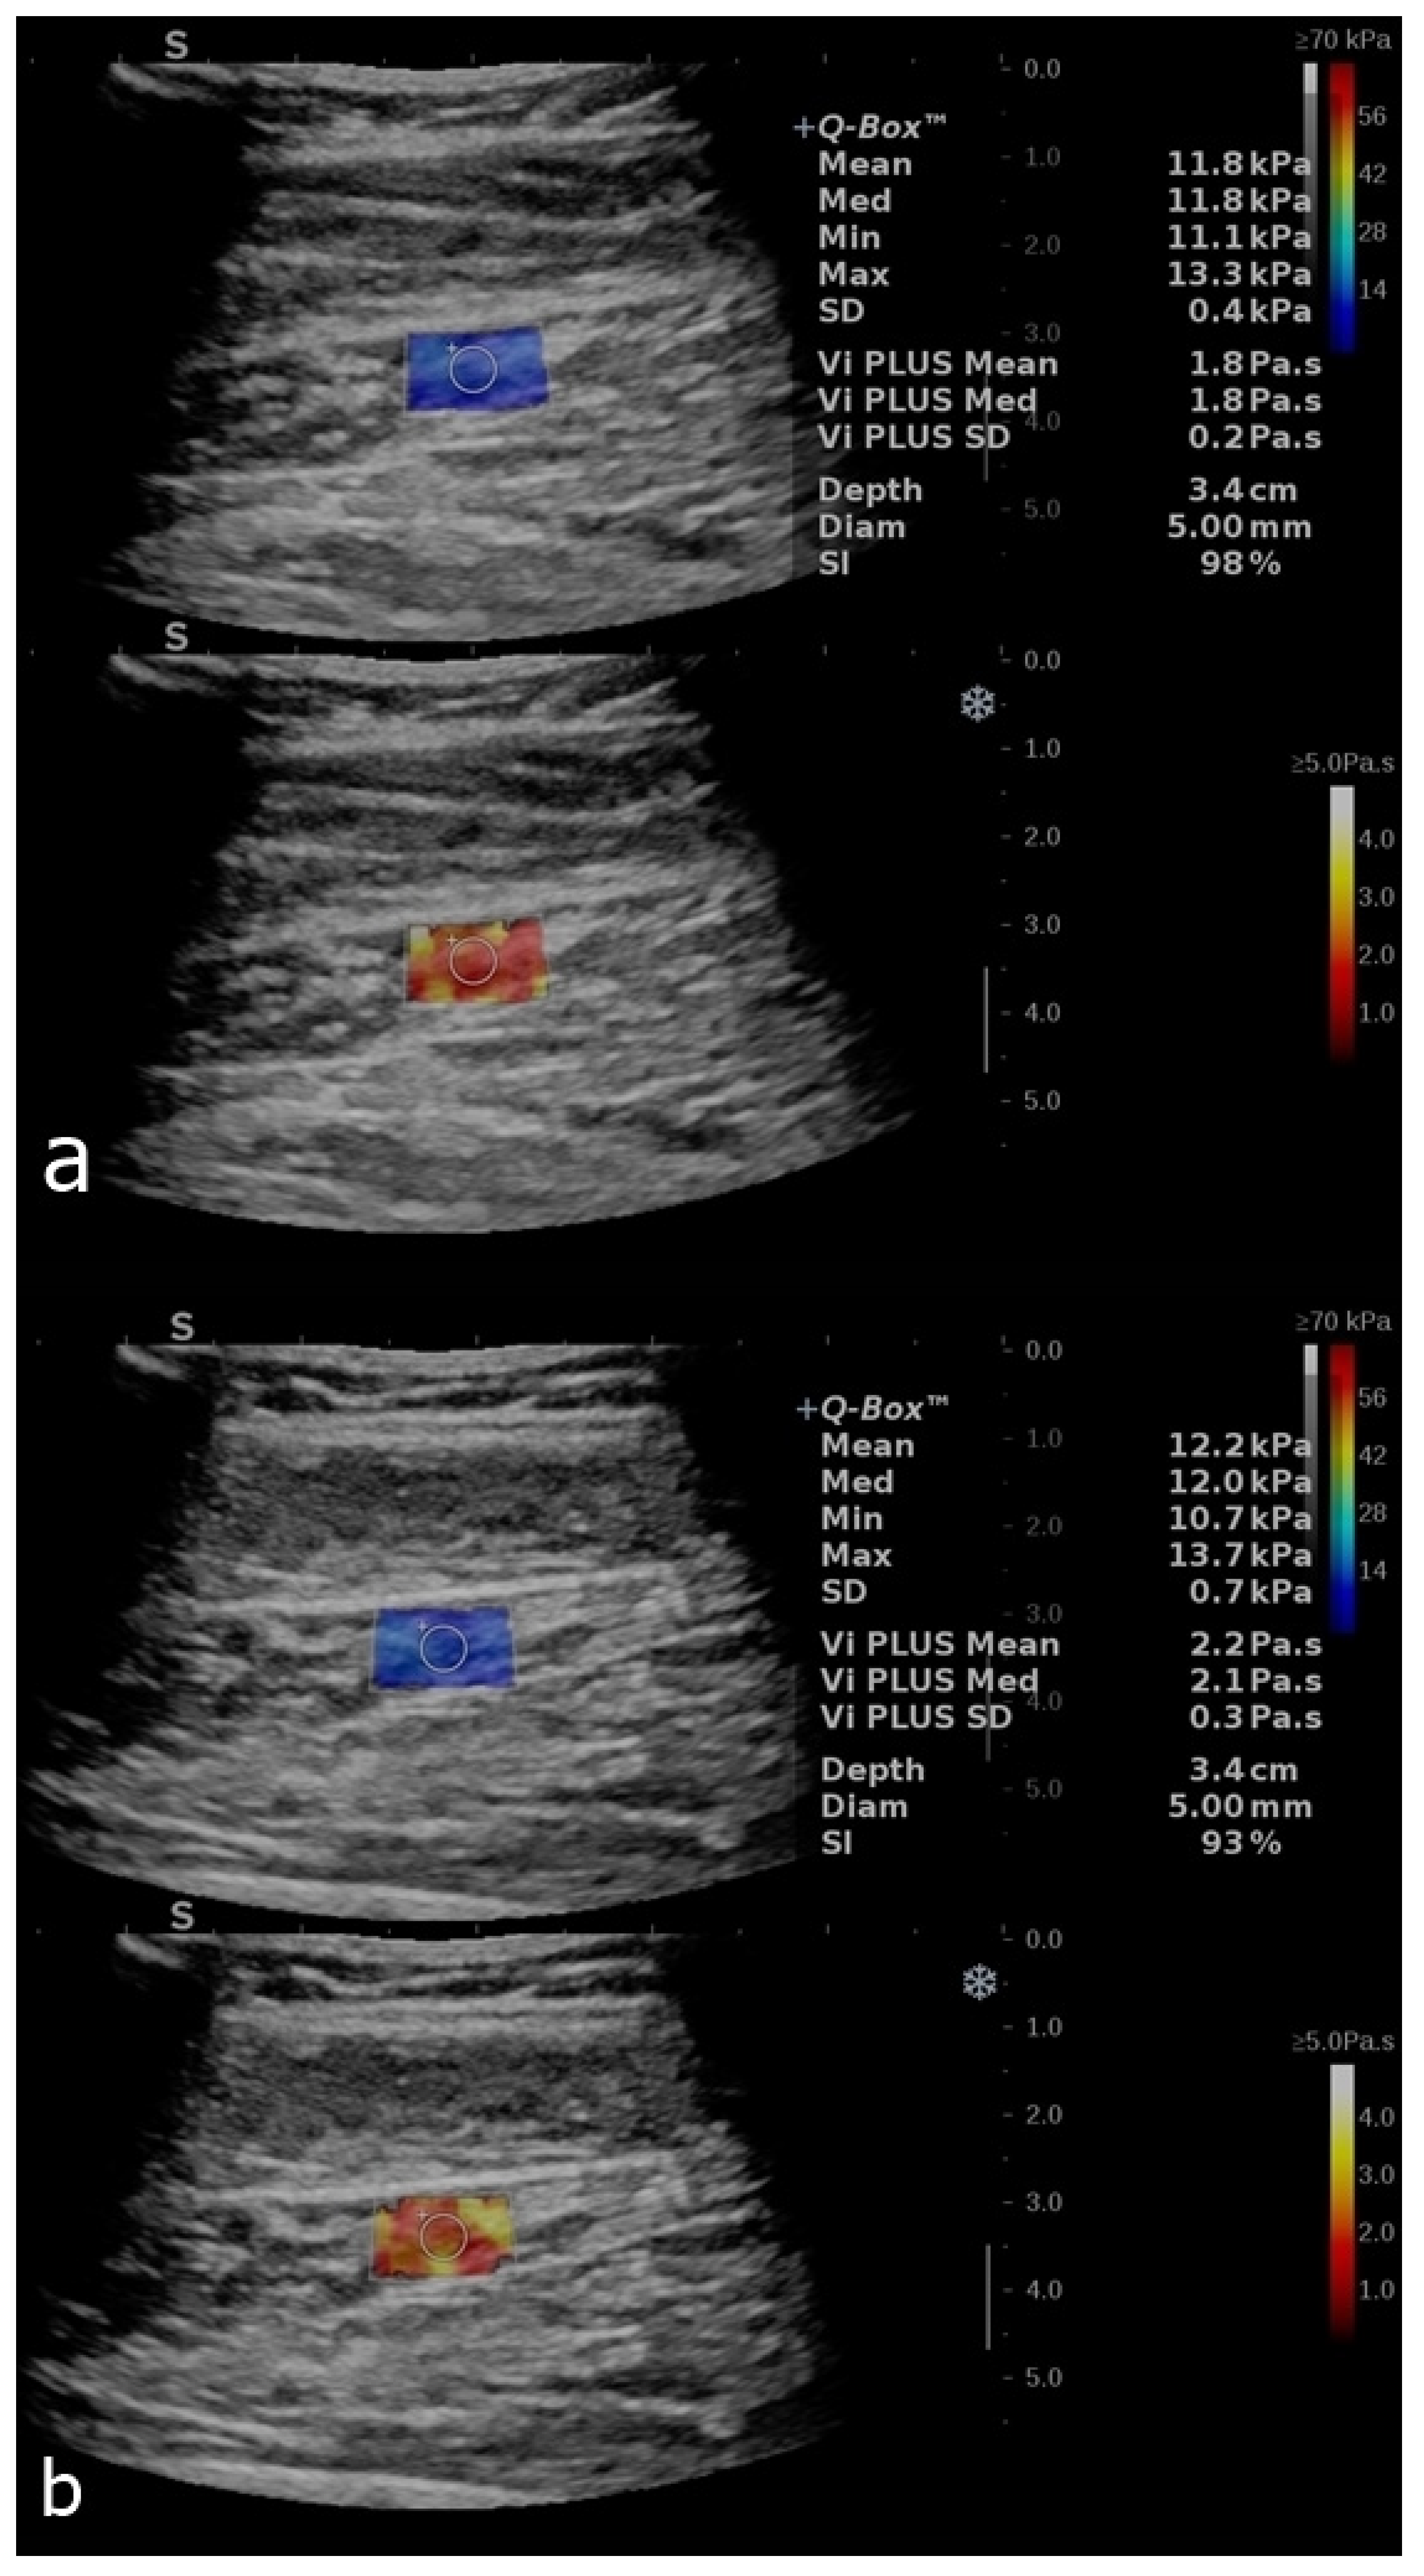

Figure 4.

B-mode image with an elastogram of the calf muscle in a healthy volunteer. Longitudinal plans of the calf muscles as follows: relaxed (a) and after contraction (b). The regions of interest (ROIs) were placed in the box when the homogenous coloring of the box was obtained with a stability index of over 90%. The top image reflects the SWE mode, and the bottom image reflects the ViPLUS application. ROI values are expressed in kPa for SWE and Pa.s for ViPLUS.